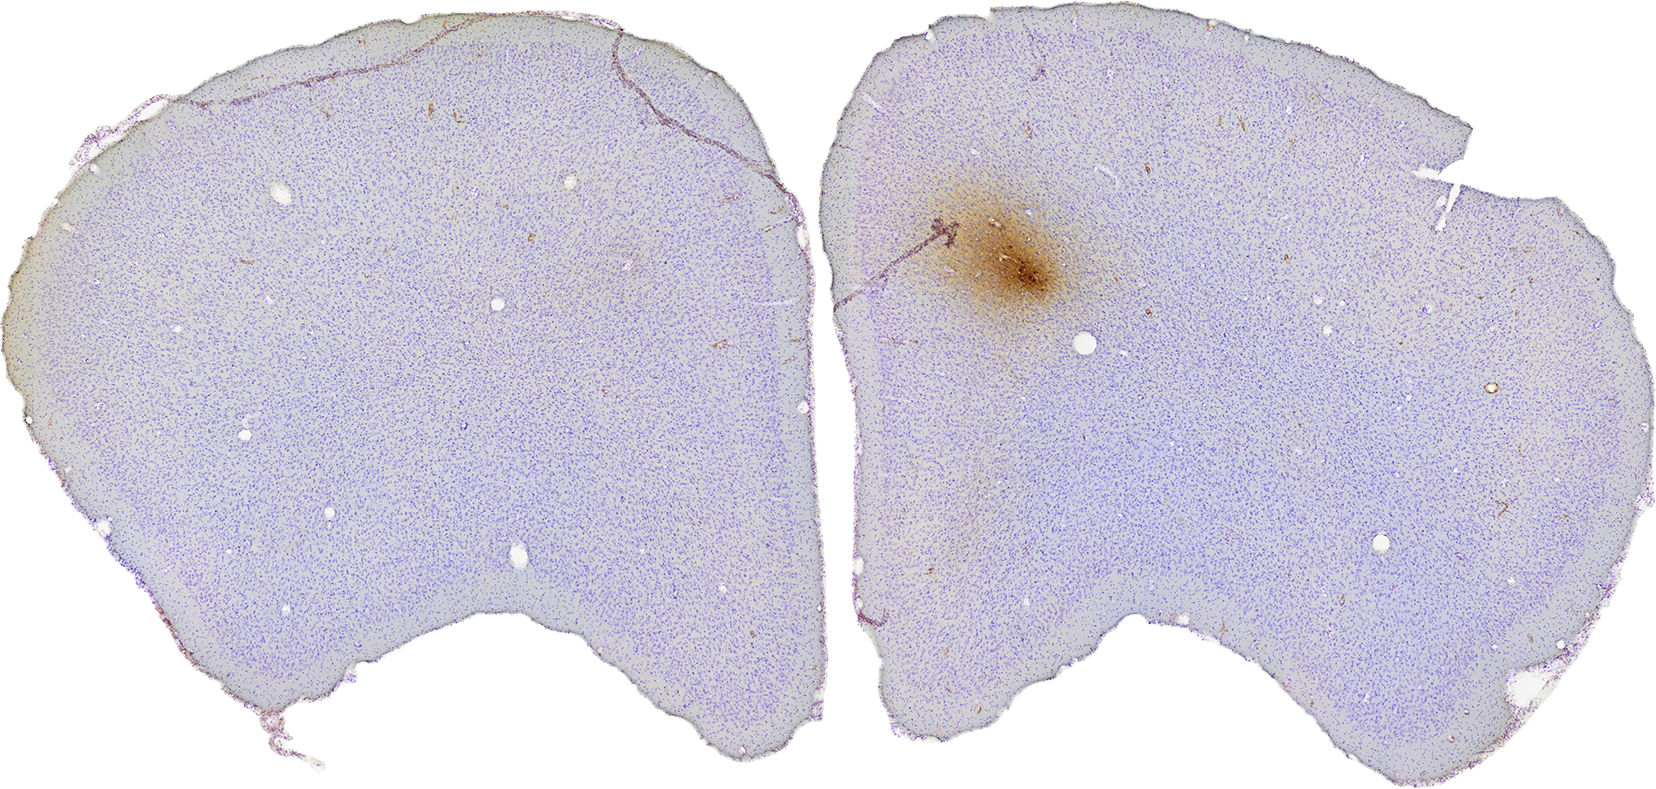

Amygdala

The amygdala is a part of the limbic system that consists of a collection of nuclei that are located in the temporal lobe. It plays a role in emotional learning,2 social cognition,3 memory and attention.2